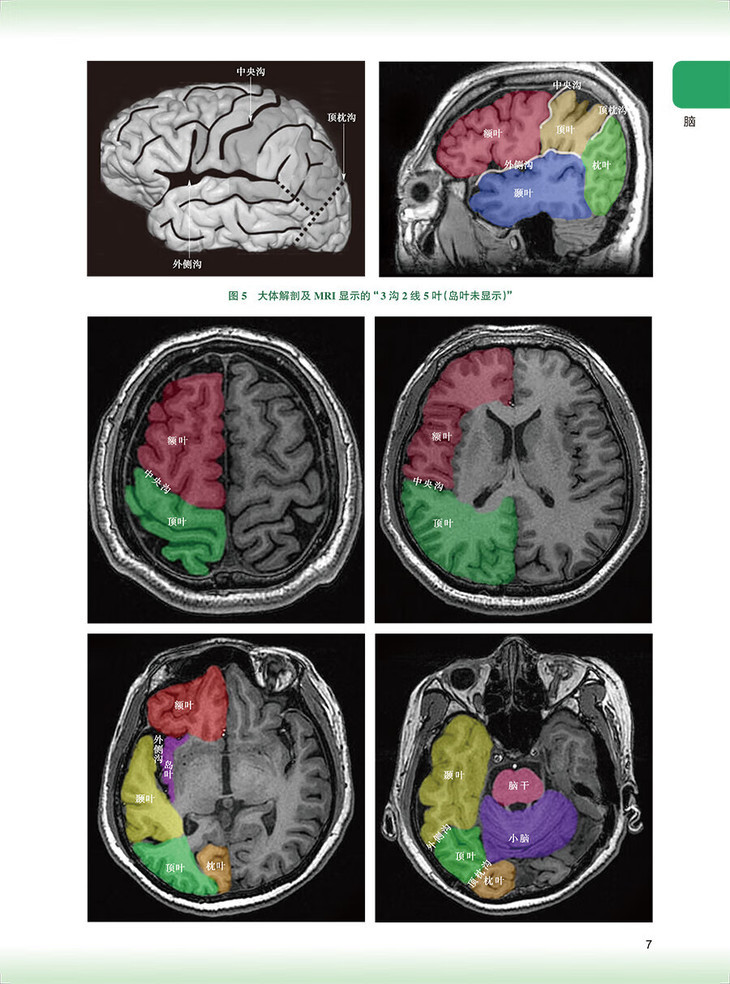

脑/1